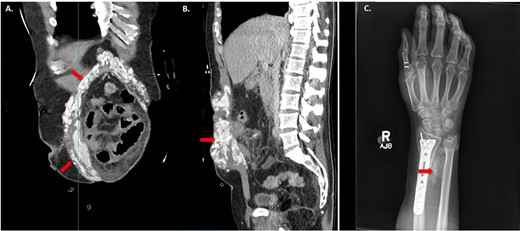

Approximately 20 days from the initial accident, the patient developed persistent fever, tachycardia, tachypnoea and swelling on the right wrist, by this time he was not able to flex forward and had limitation to his wrist movement. CT scan of the abdomen revealed advanced calcified HO surrounding the midline incision (Fig. 1A and B). In addition, heavily calcified HO to the right wrist triangular fibrocartilage between the ulnar and radius was demonstrated on ultrasound and X-ray (Fig. 1C). In conjunction with the development of his symptoms, the calcium levels increased to the range of 2.77 mmol/L to 2.87 mmol/L for 3 weeks and then returned to normal range.

HO demonstrated on computed tomography (CT) imaging and X-ray after traumatic Injuries. (A) Coronal image of HO and (B) Sagittal image of HO on CT abdomen and pelvis demonstrating sites of HO (red arrows). (C) X-ray of right forearm between ulna and radius showing HO (red arrows).